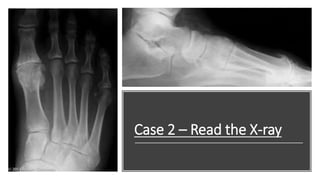

Case 2 – Read the X-ray

Case 2

This is a DP view of the right foot. The

intermetatarsal and hallux abductus angles are

normal (7 and 6 degrees, respectively). The

interphalangeus angle is slightly increased (16

degrees). Other findings include osteophytes at

the joint margins (arrows) and a loose osseous

body superolaterally (arrowheads). The first

metatarsal axis is greatly dorsiflexed relative to

the talar axis.

Diagnosis: Osteoarthritis; hallux abductus

interphalangeus; metatarsus primus elevatus.

Lateral View

This is a lateral view of the right foot. The intermetatarsal and hallux

abductus angles are normal (7 and 6 degrees, respectively). The

interphalangeus angle is slightly increased (16 degrees).

Other findings include osteophytes at the joint margins (arrows) and a

loose osseous body superolaterally (arrowheads). The first metatarsal axis

is greatly dorsiflexed relative to the talar axis.

Diagnosis: Osteoarthritis; Hallux abductus interphalangeus; Metatarsus

primus elevatus